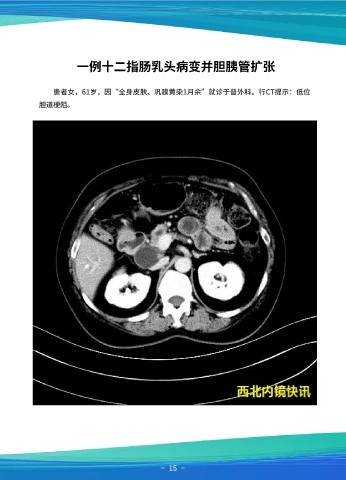

一例十二指肠乳头病变并胆胰管扩张

超声内镜示:胰腺回声正常,胰管最宽直径约2.5mm,腔内未见异常,进镜至十二                                          患者女,61岁,因“全身皮肤、巩膜黄染1月余”就诊于普外科。行CT提示:低位

指肠,胆囊显示清晰,未见结石,胆总管直径约12.4mm,下段腔内可见1枚结石影,直                                       胆道梗阻。

径约16.4x12.5mm,管壁未见异常增生。胆胰管汇合正常,乳头外形稍大,回声正常。